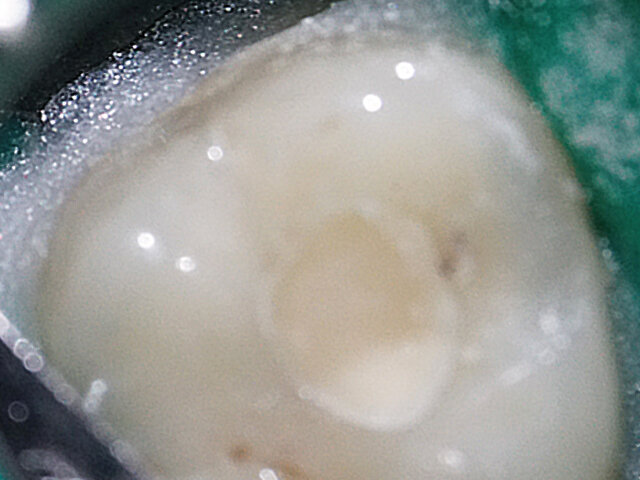

Kanálky byly dále opracovány nástrojem ProGlider, rotačním pohybem při 300 ot./min. (obr. 3). Pokud byl zjištěn odpor ještě před dosažením pracovní délky, byly kanálky vypláchnuty a břity ProGlideru očištěny. Po dosažení pracovní délky ProGliderem byly kanálky opět vypláchnuty.